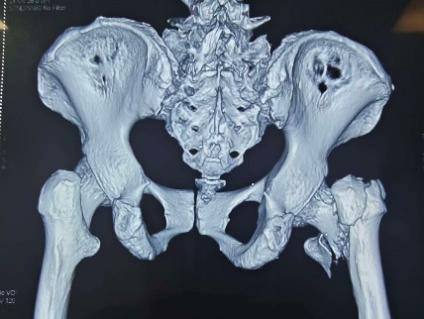

第一次内固定术后X线片及CT

此次入院前X线片及CT

怀着最后一线希望,谈大妈与家属慕名来到陕西省核工业二一五医院创伤骨科寻求诊治。吴超副主任医师接诊后,立即为谈大妈安排了详细且全面的检查,经影像检查发现,虽然粗隆间骨折已愈合,但此前植入的部分内固定物竟突破了股骨头、侵入髋臼,导致股骨头已坏死变形、髋臼骨质缺损。